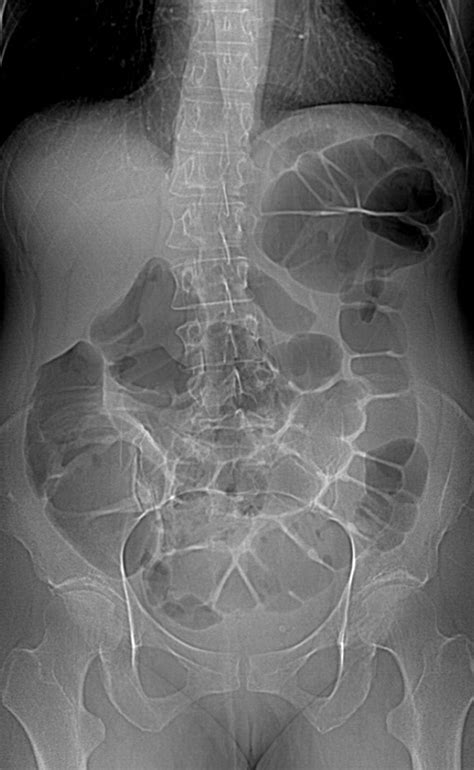

At its core, Ct Scan Colonography is a specialized radiological imaging test that produces 2D and 3D images of the large intestine. Unlike a standard colonoscopy, which involves physical exploration of the bowel, this procedure relies on computed tomography (CT) to create a detailed internal map. The process requires the patient’s colon to be inflated with air or carbon dioxide to ensure the walls of the bowel are fully distended, which allows the CT scanner to capture clear, unobstructed views of the lining.

Preparing for a Ct Scan Colonography is a critical step in ensuring the accuracy of the results. The quality of the final images is largely dependent on the cleanliness of the colon. Most facilities will require a bowel preparation regimen, similar to a traditional colonoscopy, which involves dietary changes and the use of laxatives to clear the digestive tract.

• Imaging: The patient will hold their breath for brief intervals while the scanner captures high-resolution images, usually in two positions: once while lying on their back and once while lying on their stomach (or side).